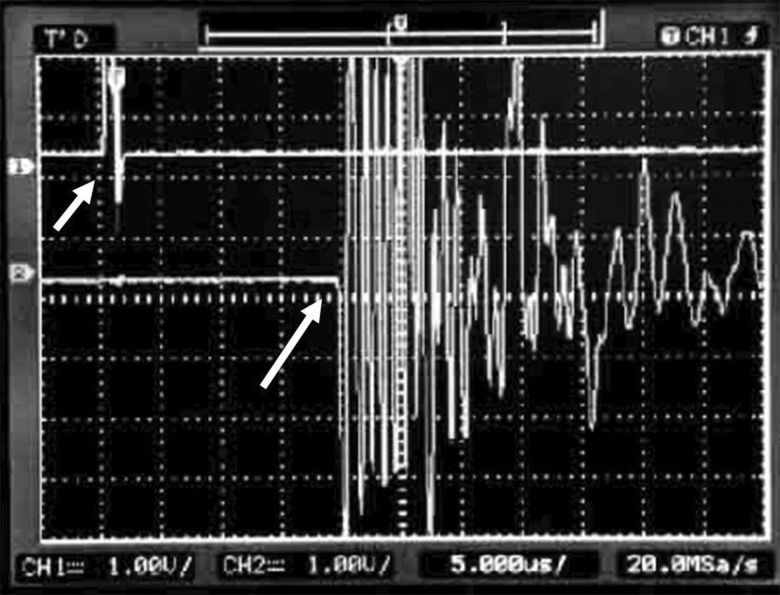

UltrasonometryTransverse underwater UV was measured with the bone segments immersed in an acoustic tank that was adapted with two unfocused ultrasound transducers (2 mm-thick PZT-5 disc, 12 mm in diameter, 1 MHz frequency), one on each of the tank in the geometric center of the walls and separated by a 25 mm distance but precisely aligned with each other along the central longitudinal axis (Figure 3). To record measurements, the two transducers, one for US wave emission and the other for reception, were connected to an ultrasound generator-receiver amplifier source (Biotecnosis do Brasil Ltda., Model US01, Ribeirão Preto, São Paulo, Brazil, www.biotecnosis.com) that could generate high power (up to 300 V) narrow (1 µs) well-defined ultrasonic pulses. The source was linked to a computer loaded with software to automatically calculate the UV based on the time of flight of the first arrived signal (FAS), as observed on a digital storage oscilloscope (Agilent Technologies, Inc., model DSO3062A, Shangai, China), together with the emitted ultrasound signal.

The FAS was defined as the first 5% positive deflection above baseline preceding the signal corresponding to the transmission mean (water) (Figure 4). The equipment was calibrated after every five measurements with a 20-mm-thick Teflon disc (constant 1274 m/s UV, at 35°C, 0.3% variation) to check for regularity and accuracy. The bone segments were positioned lengthwise in the acoustic tank supported by a Teflon stand on each end, transverse to the transducers and with the midpoint of the bone segment precisely aligned with the central axis of both transducers but closer to the emitting transducer than to the receiving transducer. The ultrasound emission frequency was 1 MHz, the pulse duration was ±1 μs, the rise time was ±0.1 ns, and the repetition time was 1 s. UV was calculated according to the formula: